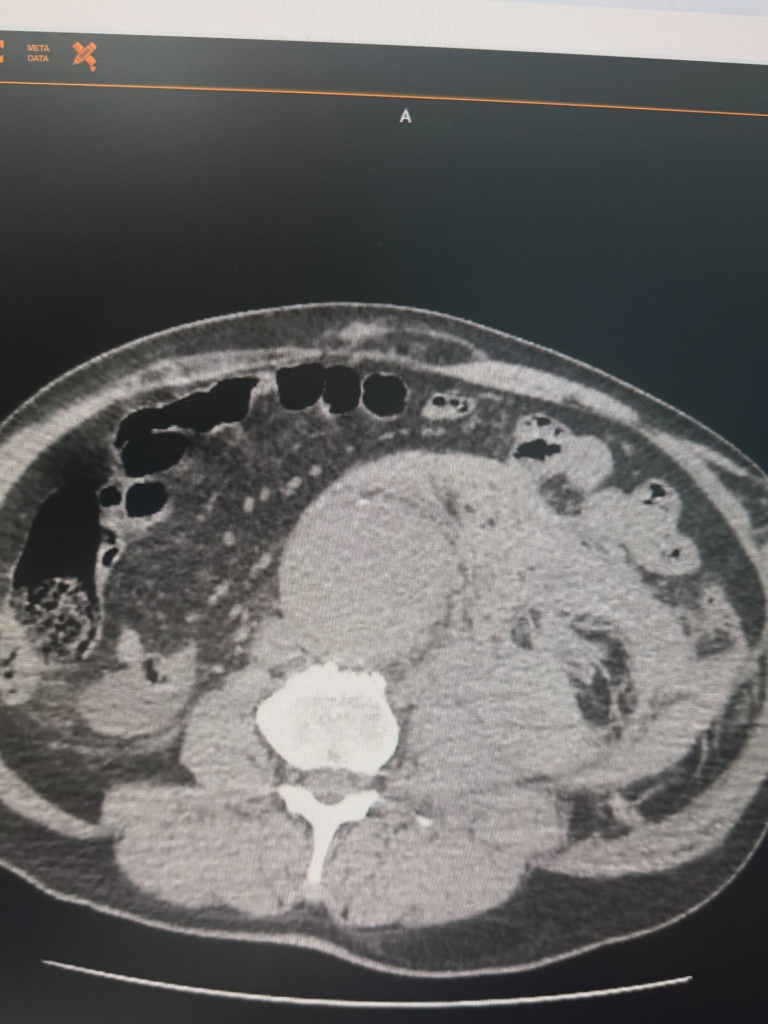

У Черкасах медики успішно врятували пацієнта з розривом аневризми черевної аорти — одного з найнебезпечніших ургентних станів у судинній хірургії.

Пацієнт перебував у критичному стані, оскільки цей діагноз належить до невідкладних і становить пряму загрозу життю. Після швидкої діагностики медики ухвалили рішення про термінову операцію.